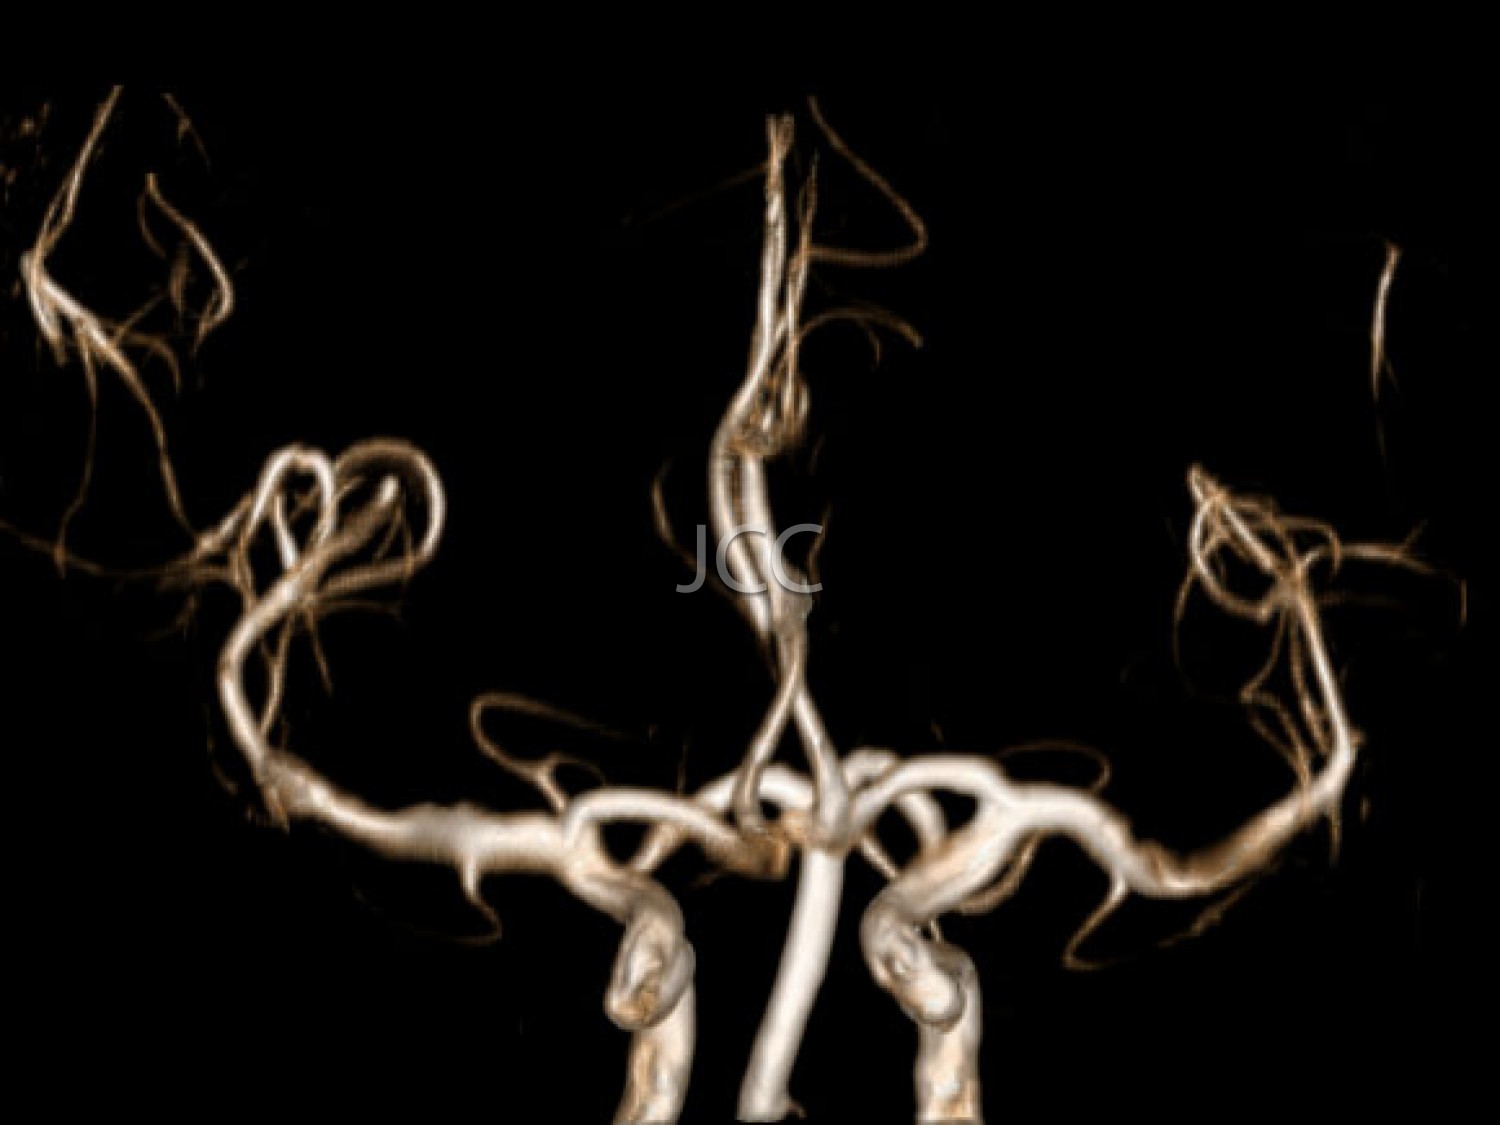

A angiografia das carótidas por TC, utilizando tecnologia de alta resolução e baixa dose de radiação, constitui o método não invasivo mais apurado, na avaliação das artérias carótidas e vertebrais, ou seja, as artérias que transportam o sangue para o cérebro. A redução do calibre por deposição de colesterol (placas) das carótidas e artérias vertebrais, é facilmente demonstrada por este método, bem como eventuais aneurismas das artérias cerebrais. A ressonância magnética permite a correcta demonstração e caracterização das malformações vasculares cerebrais, bem como a detecção precoce de inúmeras outras patologias cerebrais.